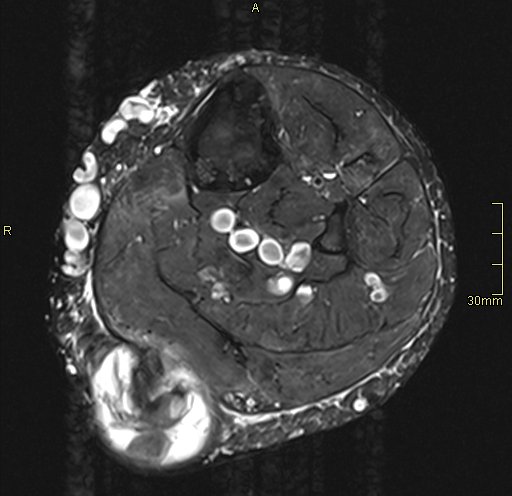

Se realiza estudio ecográfico de la «tumoración» que presenta el paciente la región postero interna de la pierna izquierda, se visualiza lesión heterogénea de 41 x 53 x 54 mm con áreas quísticas localizados sobre todo el tejido celular subcutáneo que presiona al gemelo medial, muy escasa vascularización, y áreas con sospecha de necrosis que en la ecografía se corresponden con imágenes de aspecto quístico.

La radióloga con estos datos decide ampliar el estudio con RMN donde se observa que la lesión tiene aspecto heterogéneo con áreas hipo intensas sobre todo centrales con artefacto ferromagnético con secuencias en eco gradiente que puede sugerir la existencia de restos de hemosiderina y áreas hiperintensas sugerentes de necrosis como ves en la imagen 9.

La imagen 6 te muestra un corte anatómico potenciado en T1 que nos va a mostrar relación anatómica de las estructuras. Cuando veas la imagen 7 y 8 te irás dando cuenta que la patología se muestra mucho más marcada ya que son corte axial y sagital y potenciado en un T2.

En el corte axial T2 puedes ver la gran cantidad de varices que superficialmente se observan en este corte, en formas circulares de distintos tamaños.

Puedes ver el comportamiento de la lesión en ambas potenciaciones y en al menos dos cortes ortogonales.